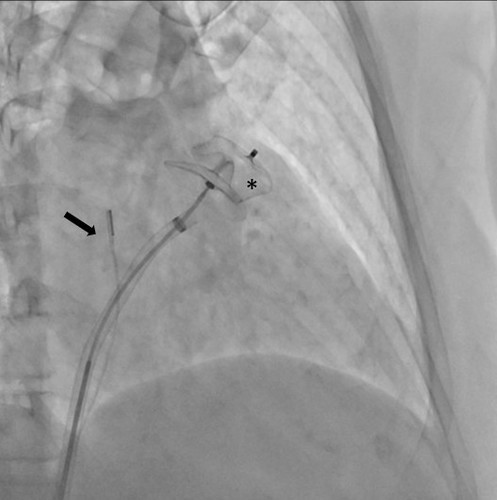

Specjaliści z Pracowni Kardiologii Inwazyjnej I Kliniki Kardiologii UCK przeprowadzili 3 zabiegi zamknięcia uszka lewego przedsionka (ang. LAAO – left atrial appendage occlusion) z wykorzystaniem systemu echokardiografii wewnątrzsercowej (ang. ICE – intracardiac echocardiography).

Zabiegi LAAO wykonuje się u pacjentów z migotaniem przedsionków i wysokim ryzykiem udaru niedokrwiennego mózgu, którzy nie mogą stosować leczenia przeciwzakrzepowego z powodu wysokiego ryzyka powikłań krwotocznych. Rutynowo przeprowadzane są one pod kontrolą echokardiografii przezprzełykowej (ang. TEE – transoesophageal echocardiography).

– U części pacjentów kwalifikowanych do LAAO ryzyko związane z wykorzystaniem obrazowania metodą TEE jest zbyt wysokie ze względu na poważne zmiany chorobowe przełyku. To dotychczas uniemożliwiało wykonanie zabiegu. Obrazowanie metodą ICE pozwala na bezpieczne wykonanie zabiegu zamknięcia uszka lewego przedsionka również w tej grupie chorych, ponieważ specjalną sondę ultrasonograficzną wprowadza się nie do przełyku, lecz przez układ żylny pacjenta, bezpośrednio do jam serca – mówi dr Dariusz Ciećwierz, koordynator Pracowni Kardiologii Inwazyjnej I Kliniki Kardiologii UCK z I Katedry i Kliniki Kardiologii GUMed. – Dodatkową korzyścią tego rozwiązania jest większy komfort pacjenta w trakcie zabiegu, dzięki czemu można uniknąć sedacji czy znieczulenia ogólnego.